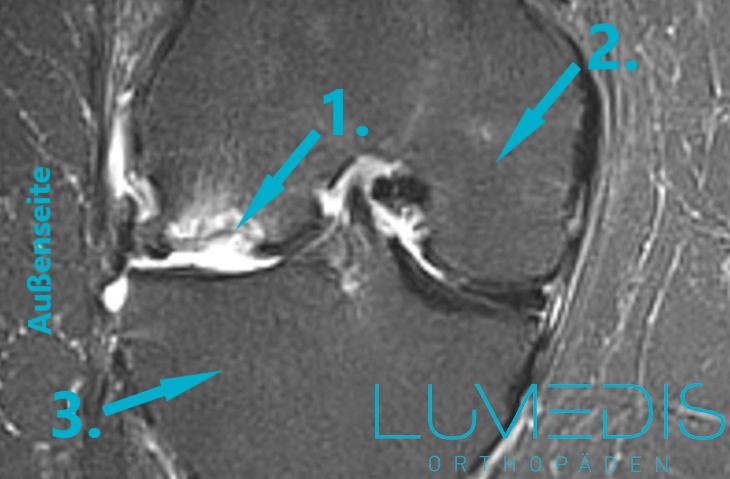

MRT eines Morbus Ahlbäck der medialen Femurkondyle (Innenrolle im Knie)

MRT einer Lunatummalazie im fortgeschrittenem Stadium